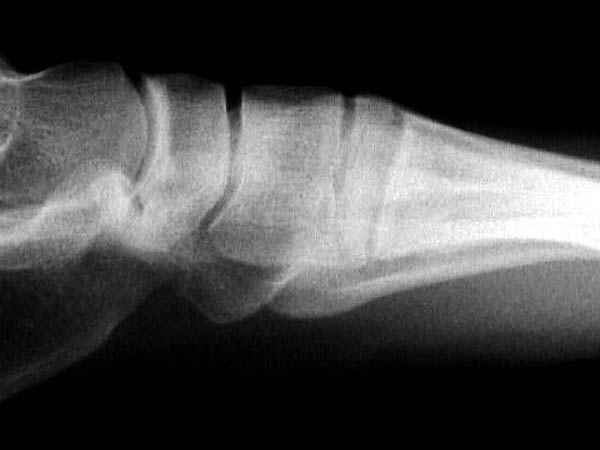

Ренген снимки прислал один из моих коллег из бывшего союза, просит совета.

К нему в клинику обратился с жалобами 24 летний

студент, получил травму две недели назад катаясь на скейтинг борд.

Ходить прихрамываяь. Небольшая отечность на тыле стопы, неврологических и сосудистых изменений нет.

Подскажите, что предпринимать больному? Снимки представлены.

Имя     : lat.jpg